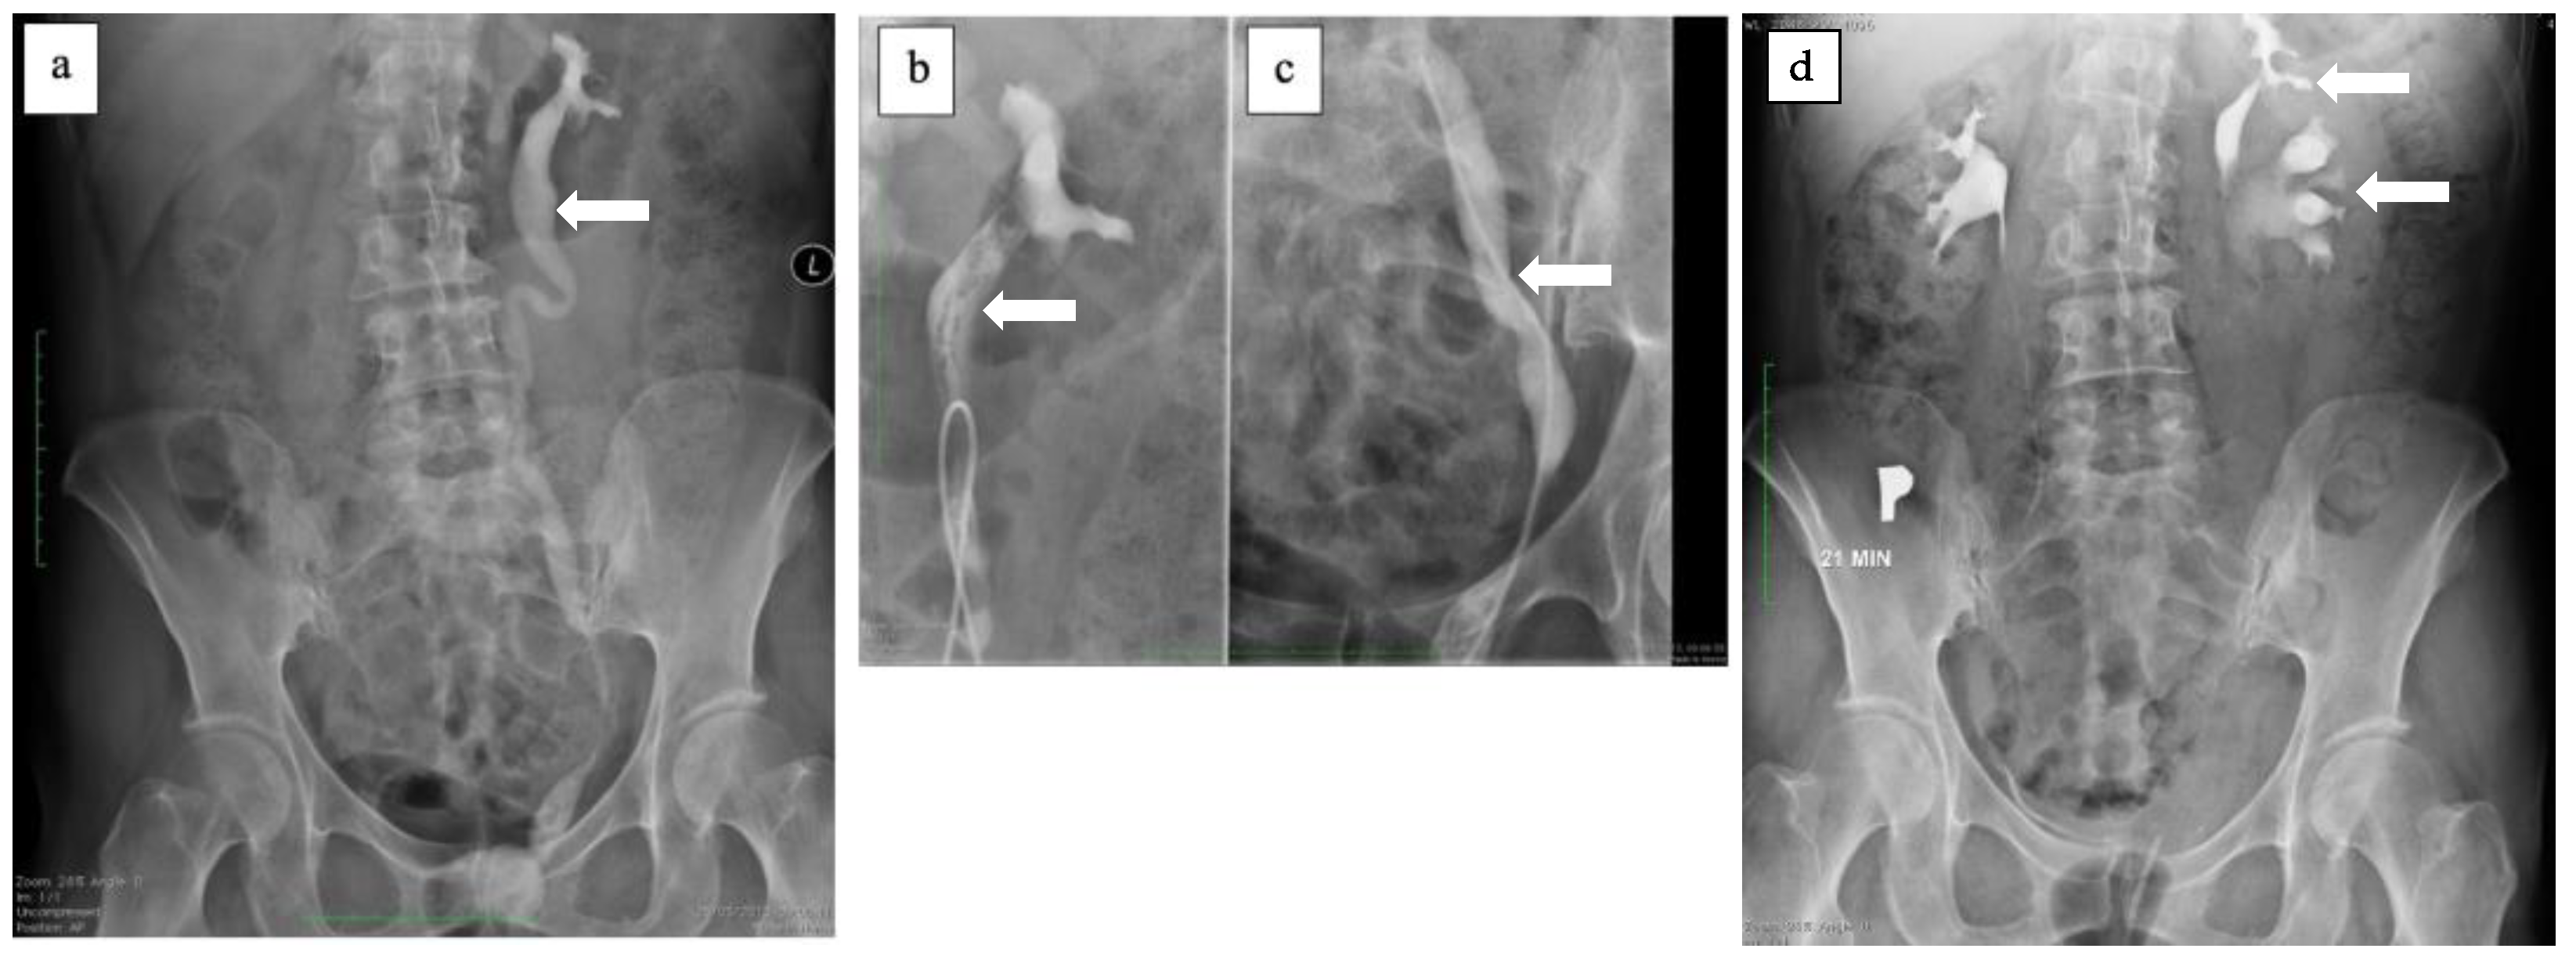

2.1. Case Study No. 1

2.2. Case Study No. 2